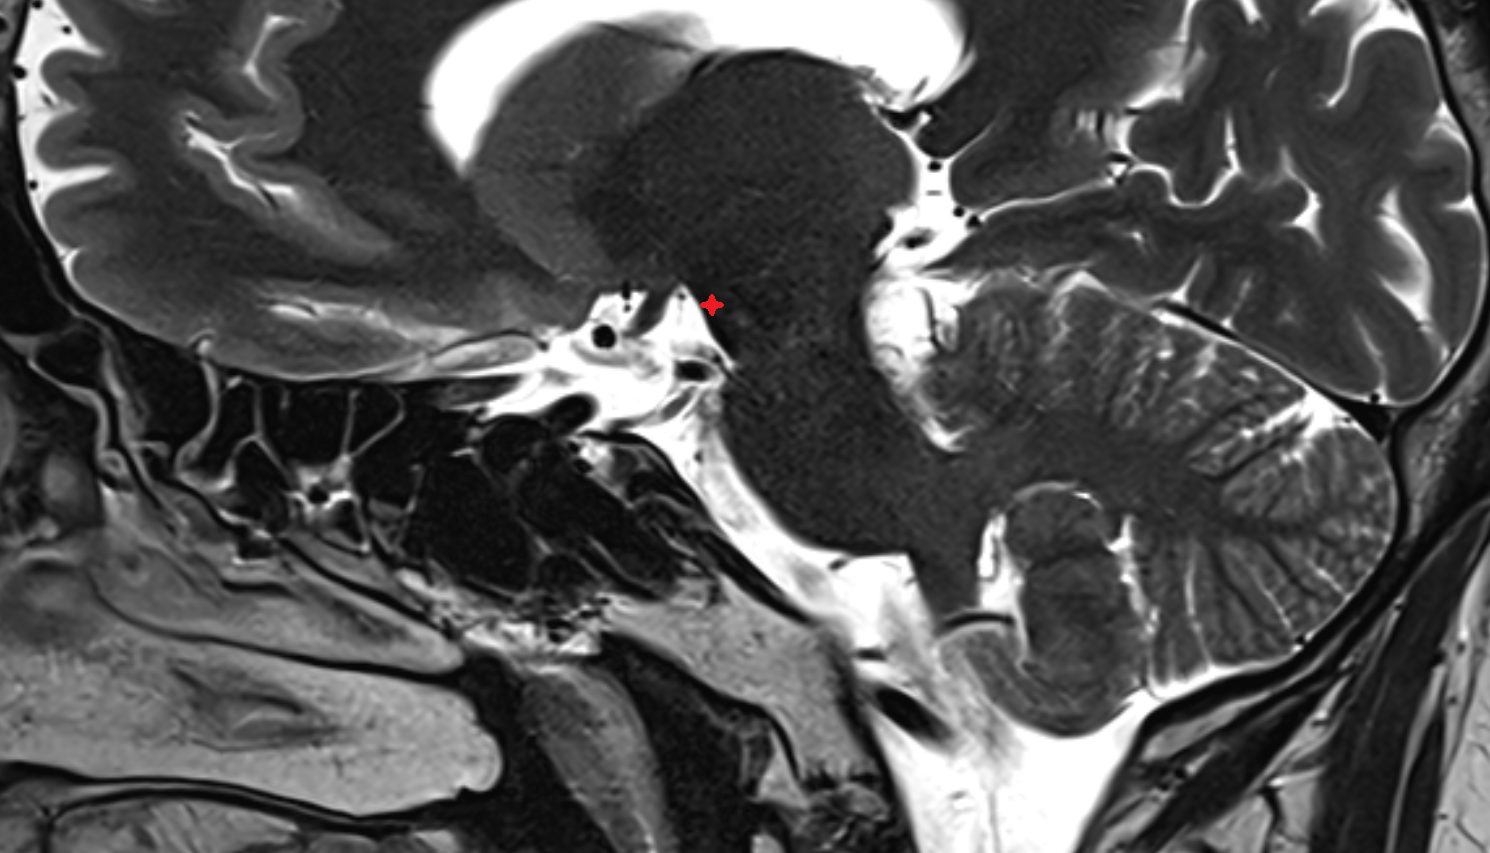

- Cisterna magna